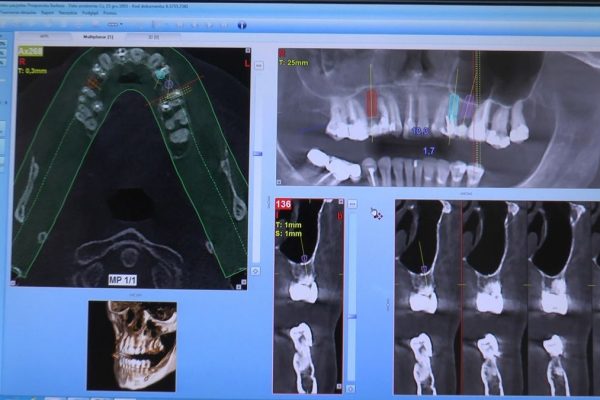

W ostatni weekend czerwca 2018 roku kursanci II Sezonu Preludium Implantologii odbyli piątą, finałową sesję, która w całości podporządkowana była praktyce. W ciągu dwóch dni zabiegowych Lekarze uczestniczący w szkoleniu przeprowadzili szereg zabiegów pod kierunkiem dr n.med. Violetty Szycik. Wszczepili 17 implantów oraz przeprowadzili ekstrakcje i zabiegi regeneracyjne kości. Zabiegi były wykonywane także w sedacji dożylnej z udziałem specjalisty anestezjologii i intensywnej terapii dr Jolanty Grzybowskiej. Preludium implantologii to nowy program edukacyjny dla adeptów implantologii stomatologicznej, którego celem jest wprowadzenie do implantologii poprzez pozyskanie wiedzy w szerokim zakresie i uwzględnieniem szczegółów mających decydujące znaczenie dla powodzenia leczenia implantologicznego. Ale tak jak wszystkie szkolenia w Instytucie Vivadental, w tym wiodące Practiculum Implantologii, zorientowane jest na praktyce i samodzielnym wykonywaniu zabiegów pod kierunkiem Mentora. To najlepsza edukacja w medycynie zabiegowej, a zarazem najlepszy start do implantologii.